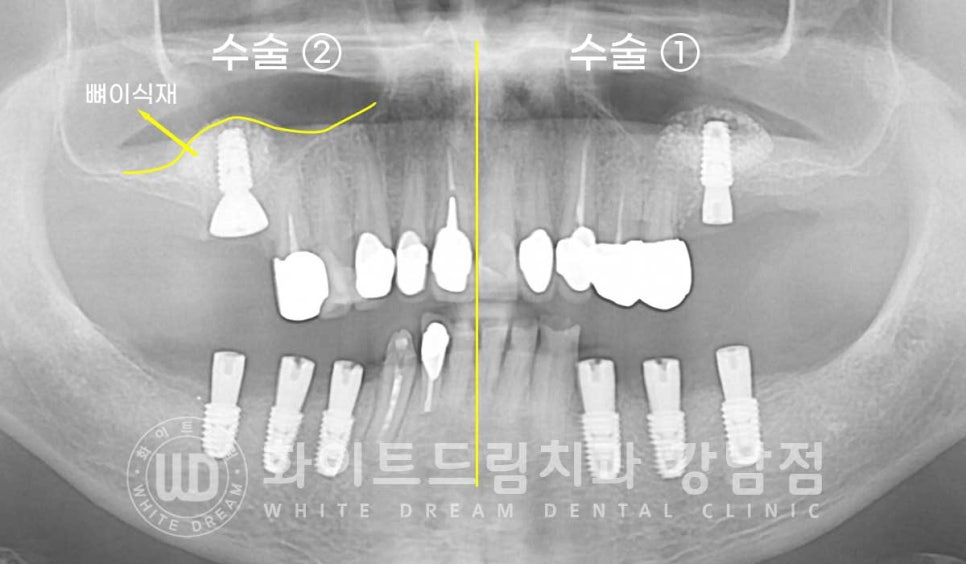

동일 인물이며 동일 환경에서 촬영됨

총 치료 기간 : 24.01.23 - 24.07.24

임플란트 개수를 줄여, 치료를 받으신 환자분의 치료 사례입니다.

상/하 양쪽 어금니가 모두 상실된 상태로 어금니 부분 틀니를 이용하여

식사를 진행하셨던 분입니다.

상악은 오랜 기간 치아가 없는 채로 생활을 해오셨기에 잇몸뼈 흡수가 심하게 진행된 상태였습니다.

상악 어금니 부분은 길이 8.5mm 직경 4.5mm의 임플란트가 들어갈 만큼의

잇몸뼈가 없는 상태로 상악동의 얇은 막을 살짝 들어 올린 후

임플란트 식립을 진행하는 상악동 거상술을 동반하였고

하악은 신경관과의 거리가 안정적으로 유지되기에 추가적인 뼈이식만 동반하여

임플란트 식립을 진행하기로 했는데요.

환자분처럼 임플란트 개수가 걱정이신 분들은

맨 뒤어금니 부위의 임플란트를 생략하여 비용부담을 줄일 수 있습니다.

환자분은 식사의 문제로 왼쪽, 오른쪽으로 나누어 수술을 진행하였고

양쪽 상악 어금니는 안내드린 대로 lateral, 측방 접근법인 상악동 거상술을 동반하여

대량의 뼈이식 후 임플란트를 식립했습니다.